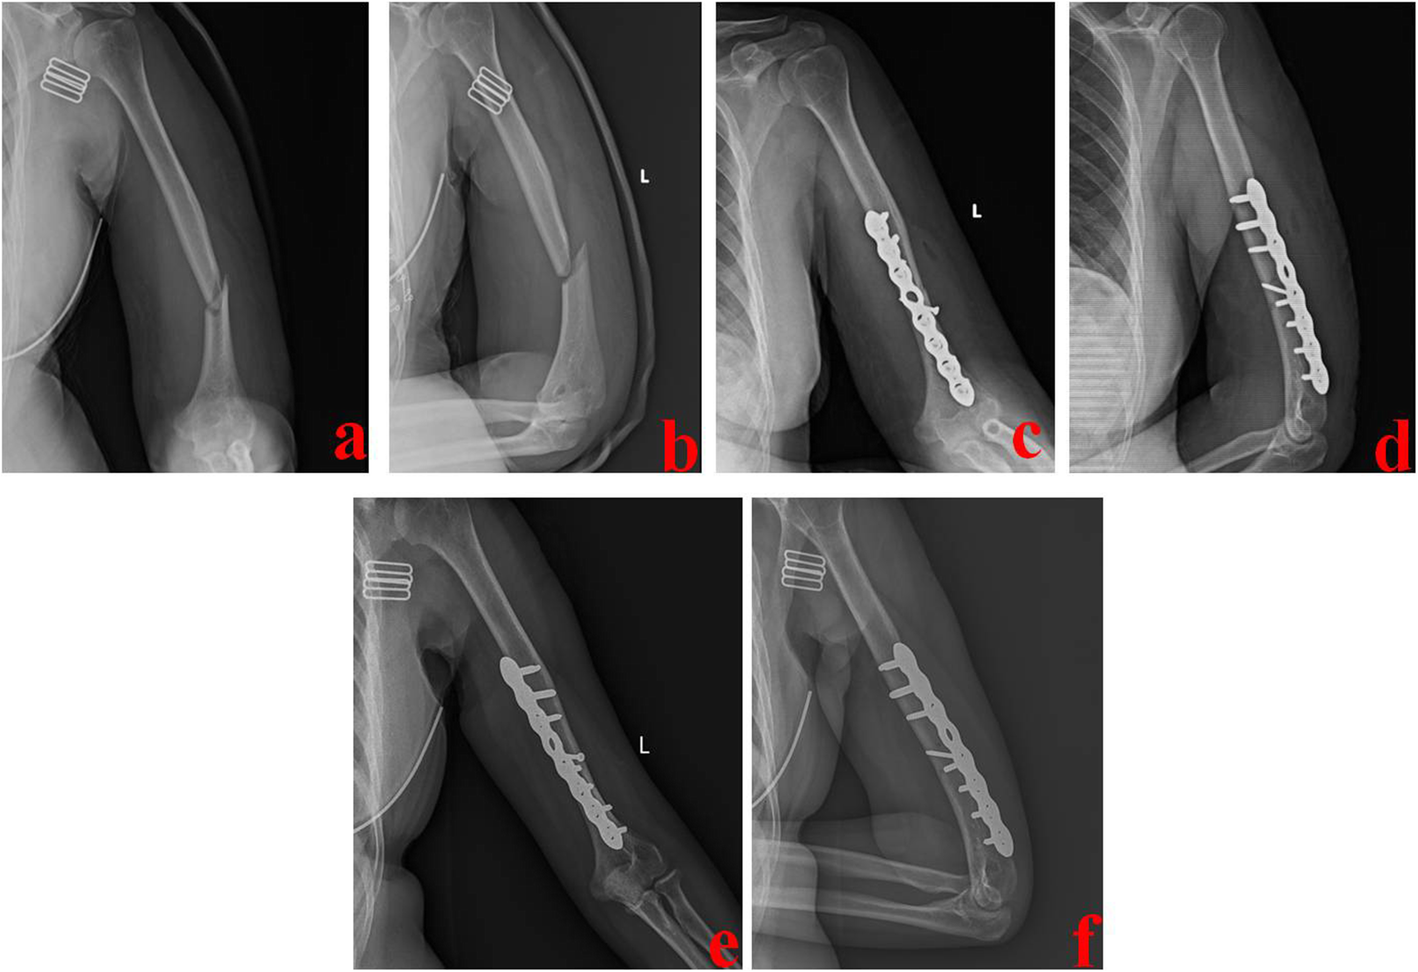

Fig. 4

A 42-year-old female was treated by PMA technique. a and b Preoperative X-ray films showed a middle and distal-third humeral shaft fracture. c and d Immediate postoperative X-ray films showed good reduction and fixation. e and f One year after operation, X-ray films showed that this fracture healed well. PMA stands for the posterior median approach